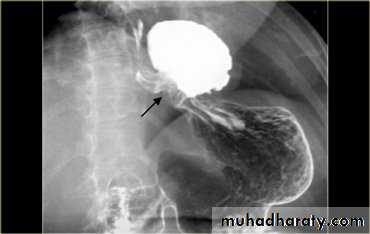

Annular Carcinoma

Narrowing :1-Constant.

2-Irrigular .

3-Variable length.

4- Shouldering sign.

5-Fistula (double tract).

6-Soft tissue shadow of the mass